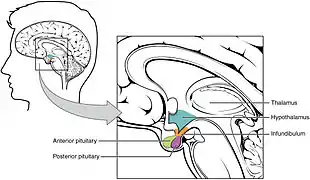

Adipsia may be seen in conditions such as diabetes insipidus[3] and may result in hypernatremia.[4] It can occur as the result of abnormalities in the hypothalamus, pituitary and corpus callosum,[5] as well as following pituitary/hypothalamic surgery.[6]

Hypothalamus

The area of the brain that regulates thirst is located in the anterior part of the hypothalamus. The anterior hypothalamus is in close proximity to osmoreceptors which regulate the secretion of antidiuretic hormone (ADH). ADH secretion is one of the primary mechanisms by which sodium and osmolar homeostasis are regulated, ADH is also secreted when there are small increases in serum osmolality. Thirst is triggered by increases in serum osmolality and along with increases ADH secretion. Both serum osmolality and ADH maintain normal ranges of serum osmolality.

Adipsia can tend to result from lesions to hypothalamic regions involved in thirst regulation. These lesions can be congenital, acquired, trauma, or even surgery. Lesions or injuries to those hypothalamic regions cause adipsia because the lesions cause defects in the thirst regulating center which can lead to adipsia. Lesions in that region can also cause adipsia because of the extremely close anatomical proximity of the hypothalamus to ADH-related osmoreceptors.[8]